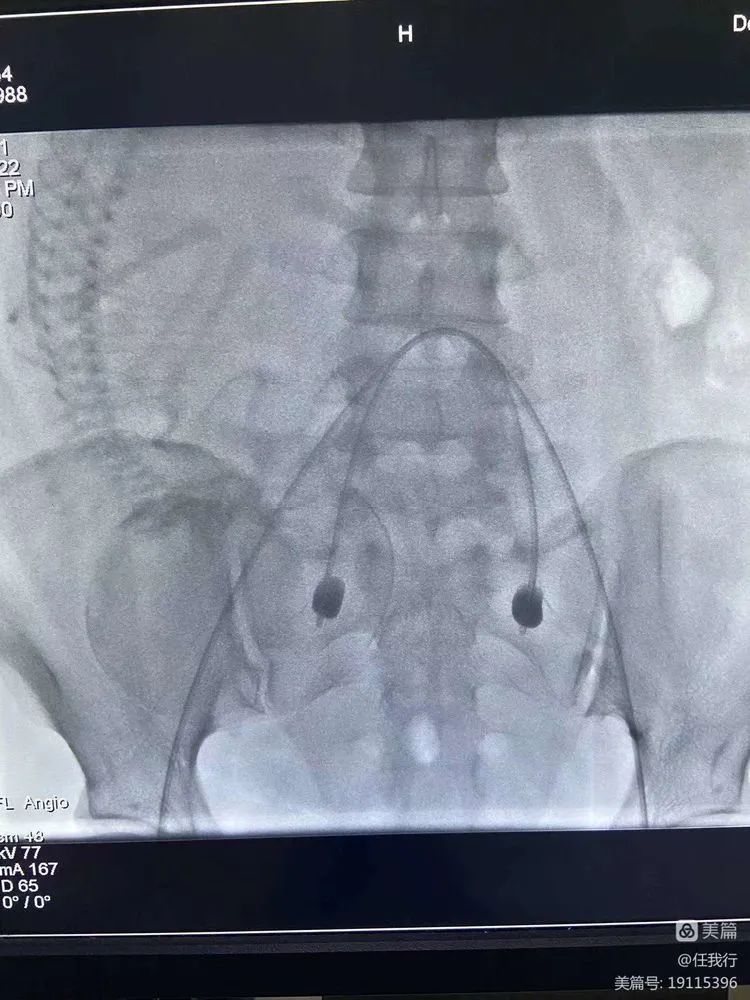

介入科醫生從大腿根部的股動脈,送兩根特制的球囊導管到腹部一根非常粗大的血管:髂内動脈(髂内動脈會給子宮提供血液)。等胎兒娩出後,将球囊擴張,完全阻塞髂内動脈的血流,然後根據具體情況處理胎盤,可顯著減少術中出血量和輸血量。如仍出血,再行明膠海綿栓塞,既可止血又能減少介入栓塞的并發症。

等産科醫生做完手術之後,介入醫生再把球囊導管的水抽出來,導管就變小了,血液又恢複了,再把球囊導管撤出來就可以了。這種創傷非常小,隻會在體表留下一個針眼小的口子。一項并不複雜的操作,卻可以解決很大的問題,相信随着介入醫學的普及,越來越多的醫院都開展介入治療,兇險性前置胎盤将不再“兇險”了。